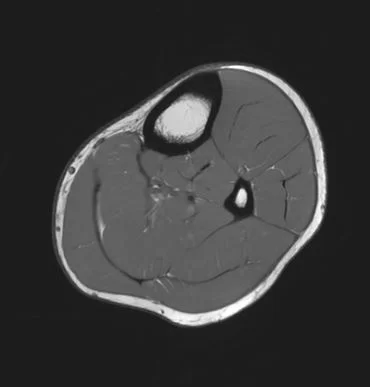

Eksempler på MR Scanninger

En MR-scanning af lårben (femur) eller underben (crus) er en sikker og smertefri undersøgelse, der giver meget detaljerede billeder af benets strukturer.

Vores 3 tesla MR-scanner bruger et kraftigt magnetfelt og radiobølger til at skabe præcise billeder af muskler, sener, knogler, knoglemarv og omgivende bløddele – helt uden brug af røntgenstråling.

Denne type undersøgelse er særligt god til at diagnosticere problemer, der ikke kan ses på almindelige røntgenbilleder, såsom vævsskader, muskeloverrivninger, seneskader og tidlige tegn på knogleskader. MR-scanning kan give et komplet billede af både de indre og ydre strukturer i dit ben.